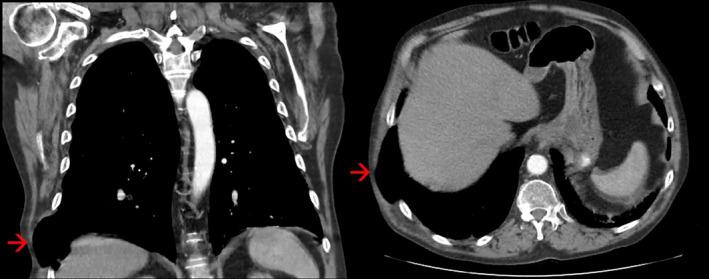

Spontaneous pulmonary hernia (SPH) is a rare condition. We report a case secondary to extreme coughing and COVID-19 infection. The patient displayed several clinical features typical of this diagnosis; difficult to manage pain on coughing, flank haematoma and bulging of the chest wall on coughing. Clinicians should be aware of the risk factors and clinical features of SPH to aid diagnosis of this rare condition.

自发性肺疝(SPH)是一种罕见的病症。我们报告一例继发于剧烈咳嗽和新型冠状病毒肺炎(COVID-19)感染的病例。该患者表现出了这种诊断的几种典型临床特征:咳嗽时难以控制的疼痛、胁腹血肿以及咳嗽时胸壁膨出。临床医生应了解自发性肺疝的危险因素和临床特征,以协助诊断这种罕见病症。